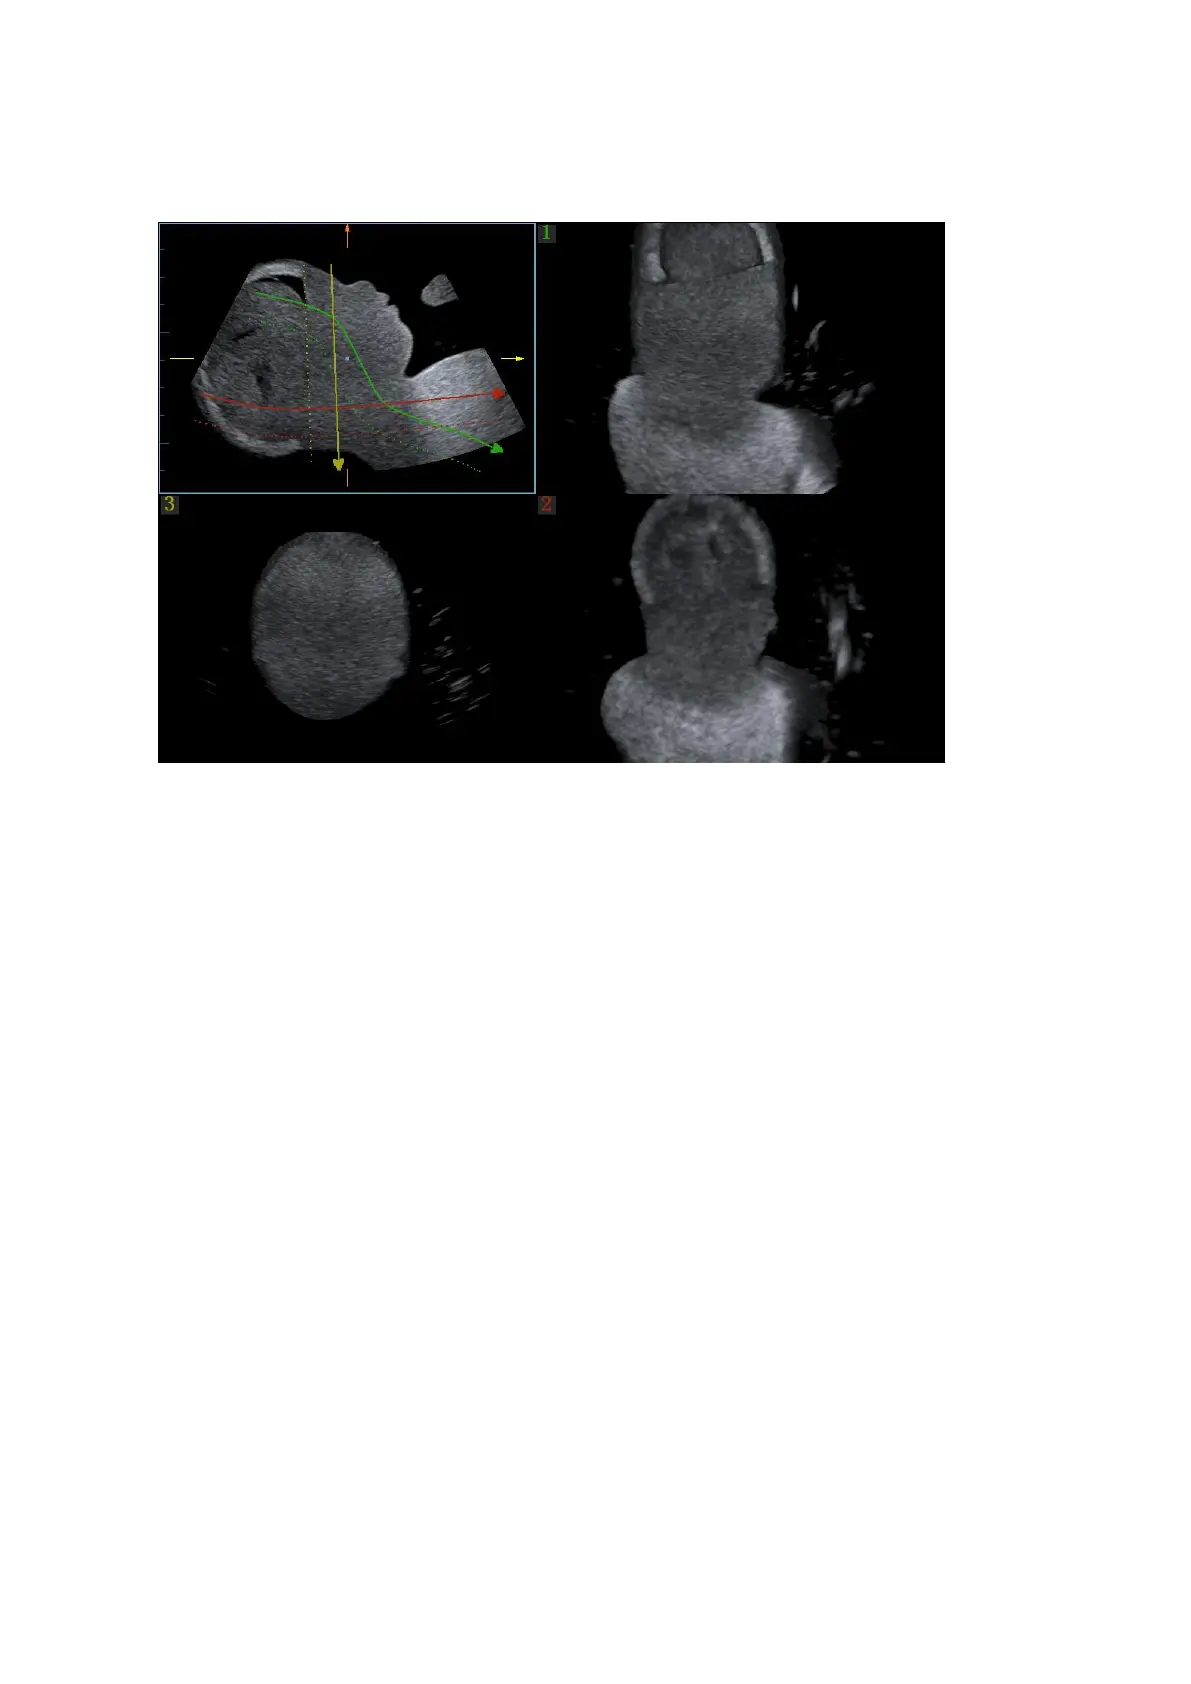

7. Draw on the reference image. You can draw three curves at most and the CMPR imaging for

the curve are displayed in the selected [1], [2] or [3] window respectively as shown in figure

below.